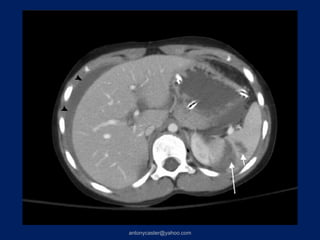

TRAUMA TÓRACO- ABDOMINAL         2da TC:(8 días después)   3raTC: ( 41 días

1ra TC: 28:07:04                             después)

IV

VIII

VII

> 3 Couinaud’s AIS90-5            HEMATOMA SUBCAPSULAR

Complicación= Biloma

V

VI

TRAUMA TÓRACO- ABDOMINAL 2da TC:(8 días después) 3raTC: ( 41 días 1ra TC: 28:07:04 después) IV VIII VII > 3 Couinaud’s AIS90-5 HEMATOMA SUBCAPSULAR Complicación= Biloma IV V VI